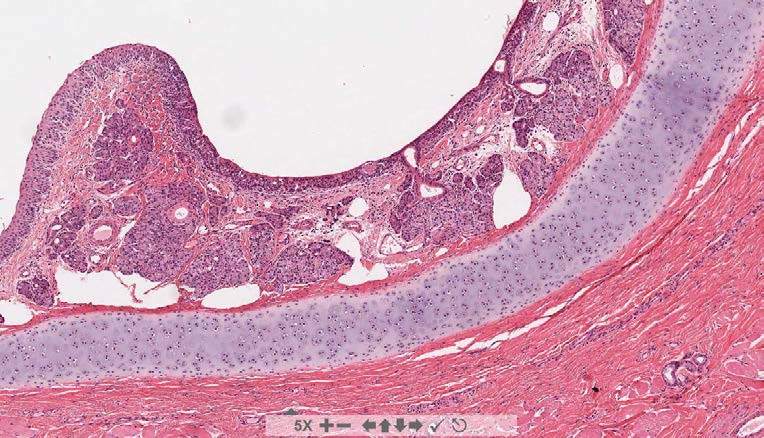

What are we looking at in this image?

trachea

rings of cartilage support the tracheal wall

a connective tissue adventitia completes the wall of the trachea